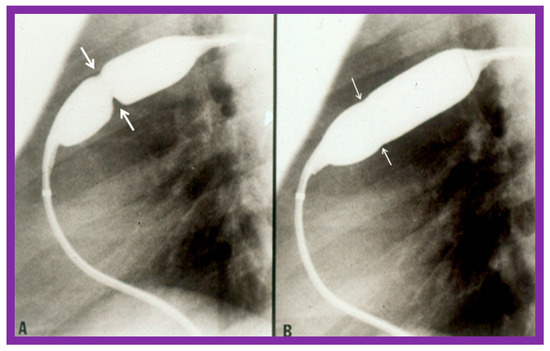

3.1. Pulmonary Stenosis

3.2. Aortic Stenosis